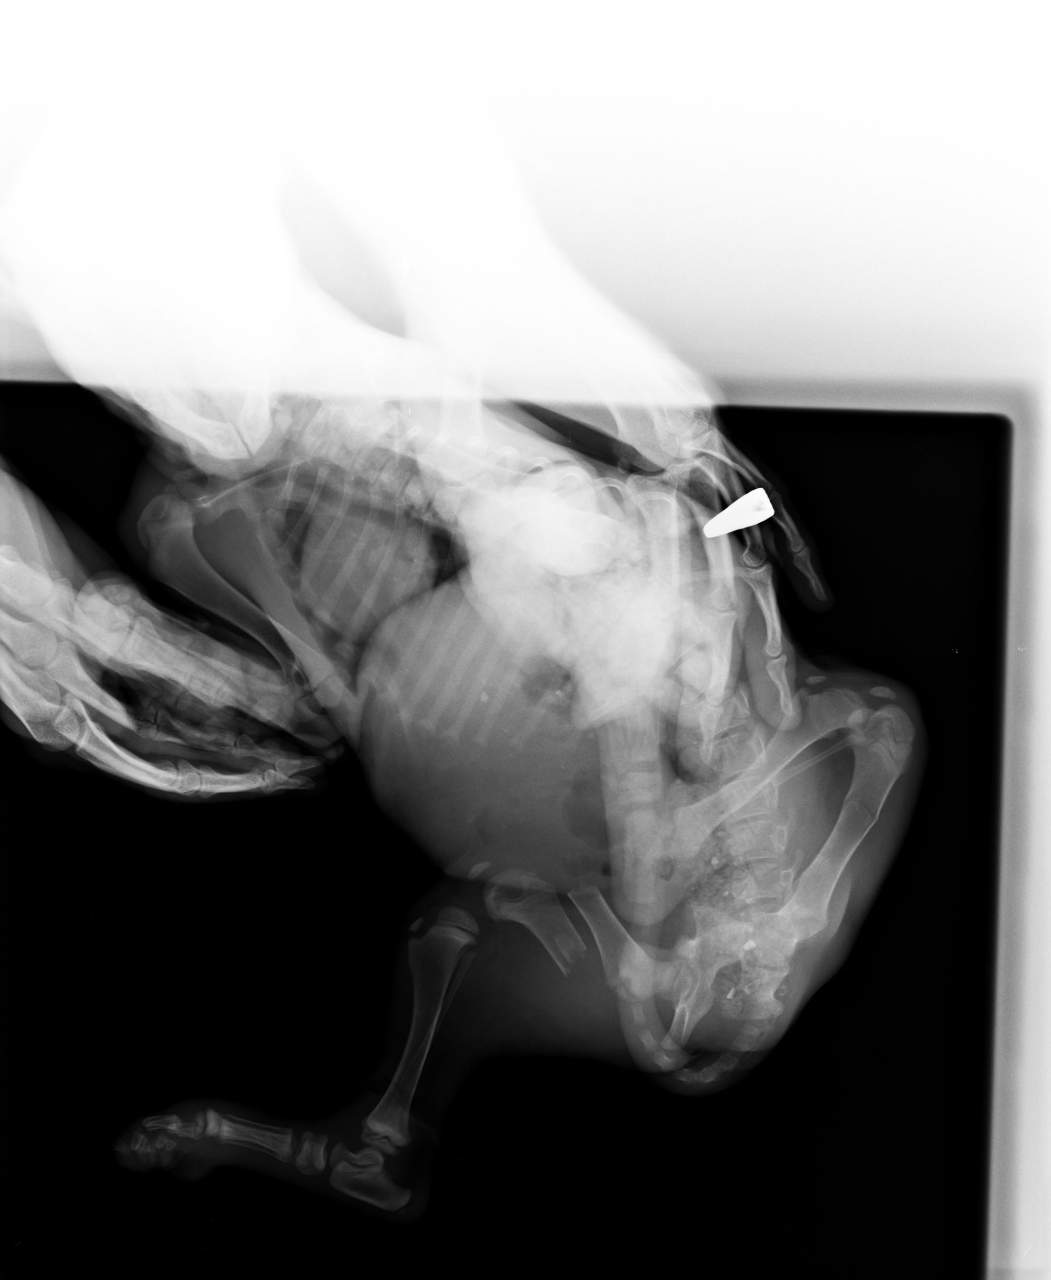

Примерно четыре месяца назад в клинику Калипсо молодой человек принес искалеченного щенка, полутора месяцев от роду. У неё был раздробленный таз и сломано бедро, она попала под машину. Малышку прооперировали и всё это время она жила в клинике, где её кормили, лечили, вакцинировали. За это огромное спасибо врачам, они не только дали ей шанс выжить, но и сохранили лапку. Но у Багиры не было куратора, человека, который взял бы на себя ответственность за её восстановление и заботу о её дальнейшей судьбе.

Ещё мы планируем свозить Багиру на рентген и на консультацию, чтобы определить, что можно предпринять, чтобы лапка заработала.